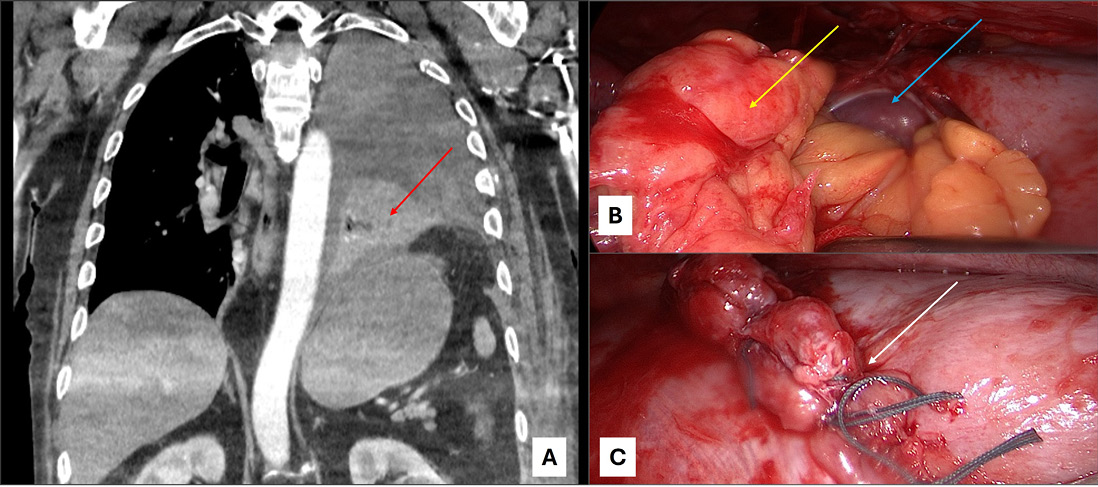

Abb. 1: Akutversorgung Polytrauma; Grenzwertig kardiorespiratorisch stabiler Polytraumapatient (Injury Severity Score: 34) mit Spannungspneumothorax, thorakaler Blutung und weiteren Verletzungen. Primärmaßnahmen: Entlastungspunktion Thorax rechts und Anlage Thoraxdrainage. Bei weiterer thorakaler Blutung, jedoch stabilisierten Verhältnissen, primäre thorakale Versorgung mittels VATS (Videoassistierter Thorakoskopie) und Rippenosteosynthese. A. eingebluteter rechter Lungenunterlappen im WB-CT (schwarzer Pfeil). B. In die Lunge einspießende Rippe (roter Pfeil). C. Durch dislozierte Rippe eingerissener und blutender Lungenunterlappen (gelber Pfeil). D. Abschlussbild mit Rippenosteosynthese (grüner Pfeil).

Abb. 3: Traumatische Zwerchfellverletzung; Legende: Traumatische Zwerchfellruptur links. A. Hämatoserothorax links. Rupturstelle (roter Pfeil) mit nach intrathorakal verlagerten Gewebeanteilen aus dem Abdomen. B. VATS links: Omentum majus Anteile (gelber Pfeil). Milz (blauer Pfeil). C. VATS links: Zwerchfellnaht (weißer Pfeil).